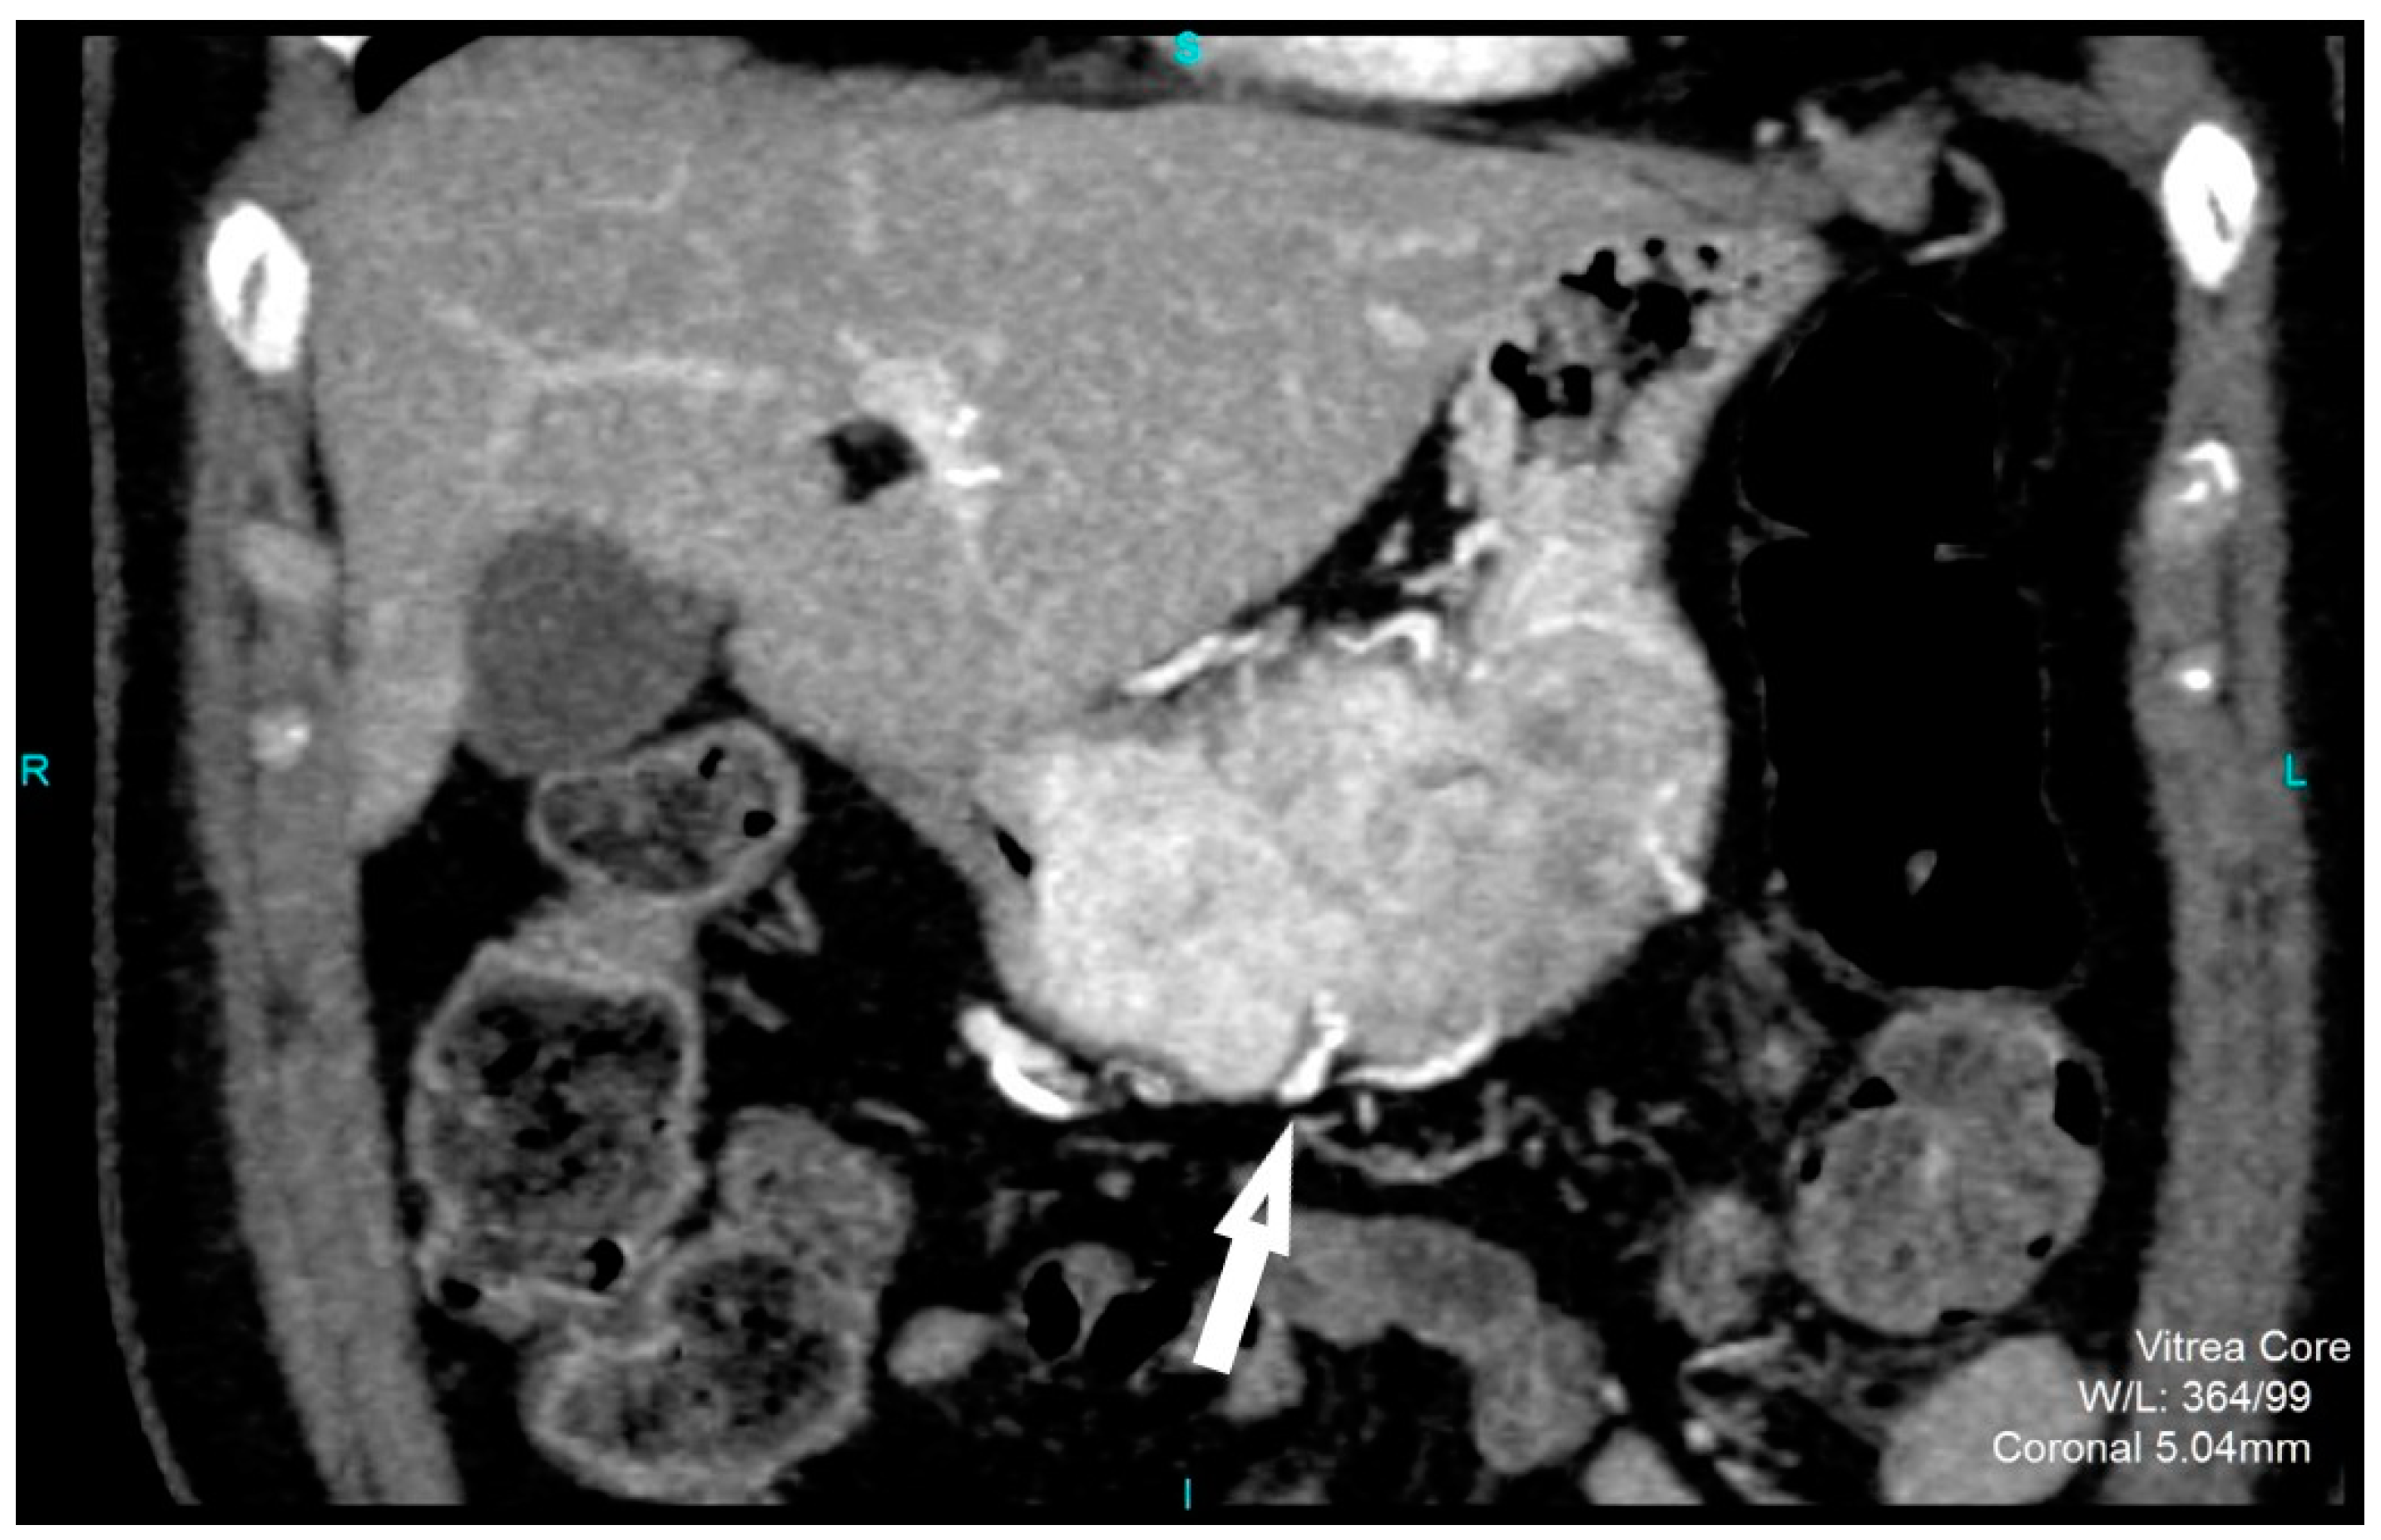

CT imaging features were analyzed as follows: maximal diameter in the axial slice and tumor structure, which was classified into cystic and solid/necrotic. The shape was depicted as regular or irregular. Tumor localization considered the body of the stomach, antrum or pyloric region. Mucosa was observed in two ways: intact/continuous or disrupted. Growth patterns were categorized as exophytic/mixed or endophytic. The degrees of enhancement of the solid part of tumor tissue were divided into weak, moderate or obvious enhancements. The presence of enlarged feeding or draining vessels (EFDV) was also recorded, as was the presence of metastasis in liver and other organs ( Figure 1, Figure 2 and Figure 3).

Figure 2. Contrast enhanced CT, coronal view, shows high risk GIST in a 69-year-old female patient, with a clearly demarcated submucosal lesion in the antrum of the stomach with an exophytic growth pattern and predominantly cystic structure with the strong post-contrast enhancement of solid part of tumor (arrows) (a). CT examination, coronal section, in a 49-year old female patient reveals intraluminal predominantly solid tumor lesion with irregular shape and margins, endophytic growth with the discontinuity of gastric mucosa and obvious post-contrast enhancement in a HR GIST (b).